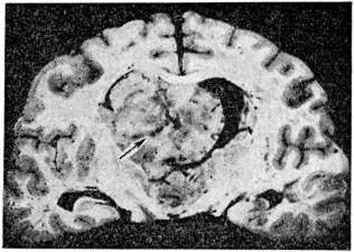

Макроскопически Олигодендроглиома имеет вид узла, чаще нечётко отграниченного от окружающего мозгового вещества (рисунок 1). Ткань опухоли однородного сероватого, серовато-розового, реже красноватого цвета, консистенция либо соответствует мозговому веществу, либо студенистая с наличием мелких кист.